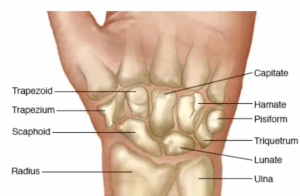

Broken wrist

A broken wrist is a break or crack in one or more of the bones of your wrist. The most common of these injuries occurs in the wrist when people try to catch themselves during a fall and land hard on an outstretched hand.